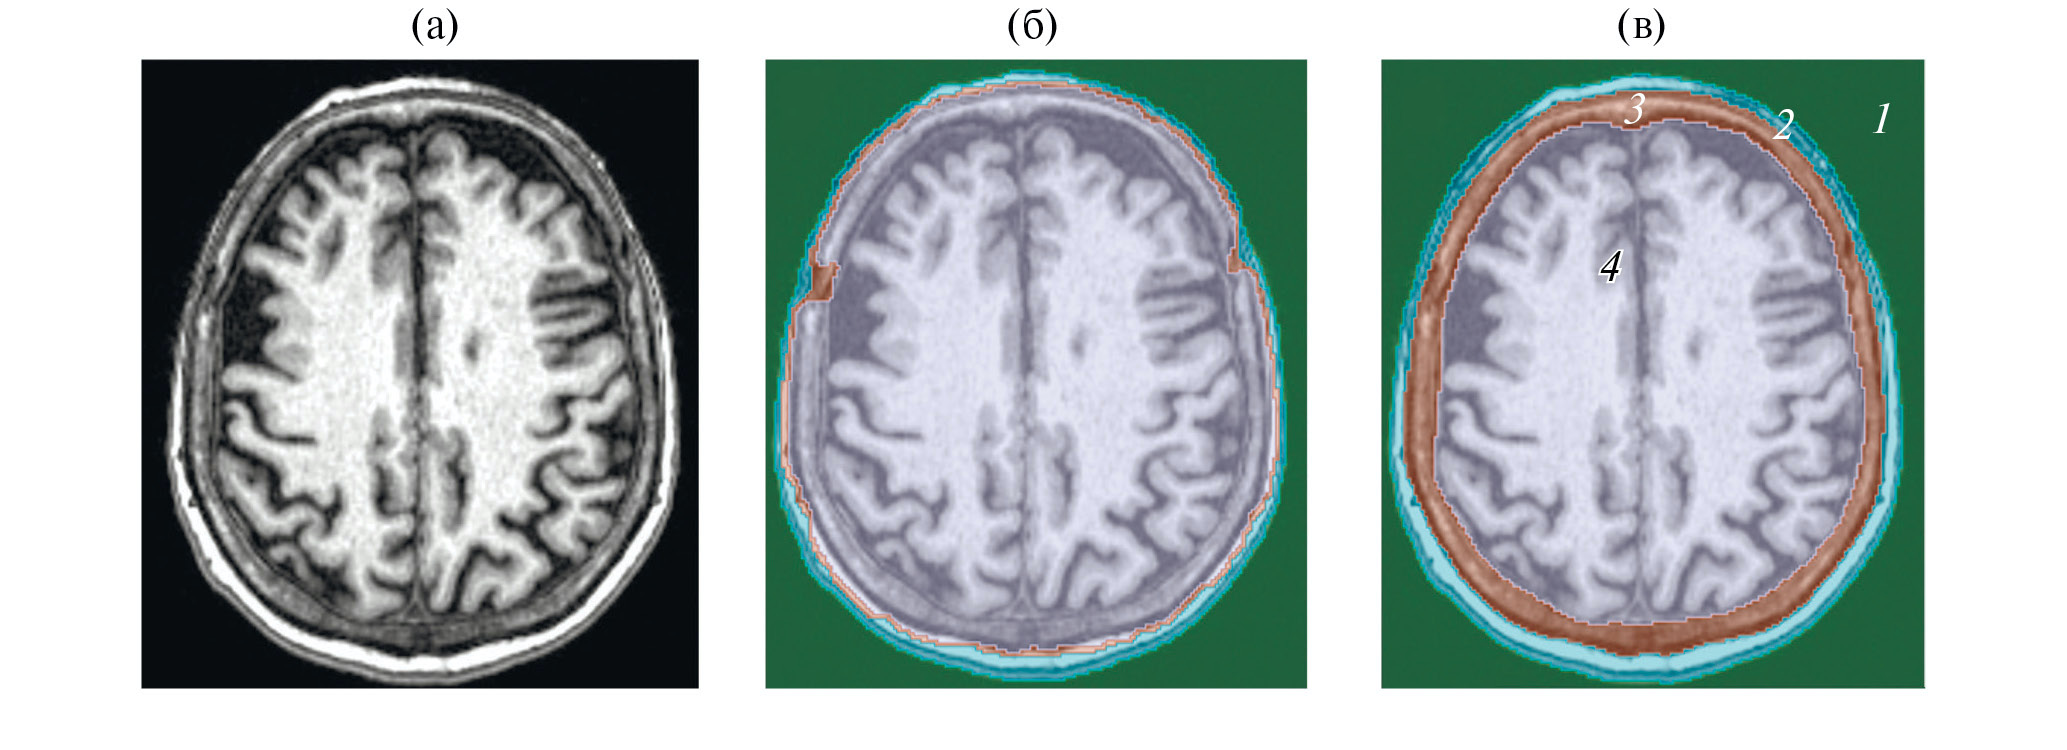

Данные МРТ представляли собой T1-взвешенное трехмерное изображение с набором из 176 аксиальных срезов с разрешением 1 × 1 × 1 мм. В отличие от КТ-изображения, МРТ предоставляет только качественную визуальную информацию о тканях и органах. Сегментация МРТ-изображения была проведена в два этапа. На первом этапе изображение сегментировалось в программе открытого доступа BrainSuit21a (brainsuite.org), однако из-за ограниченного разрешения МРТ-изображения и анатомических особенностей строения головы человека (наличия зрительных нервов и т.д.) выделение границ черепа с использованием детектора Марра–Хилдретта, используемого в программе BrainSuit21a, дает неточности [21, 22]. Поэтому, для более точного определения границ тканей, сегментация была доработана вручную в программе Slicer, ориентируясь на визуальные границы анатомических структур (рис. 2) [20].

Рис. 2. Аксиальный срез магнитно-резонансной томографии головы человека (а) – до сегментации; (б) – после сегментации в программе BrainSuit; (в) – после доработки в программе Slicer. Цвета сегментов соответствуют таковым на сегментации КТ.